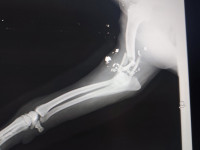

Sonia und Carmen haben einen Beagle mit einem zerschossenen Bein gefunden. Sie sind sofort mit ihm in die Tierklinik gefahren. Der Tierarzt hat einige Splitter und Kugeln aus der Schusswunde am Ellenbogen entfernt. Nun bekommt der Hund Antibiotika, Entzündungshemmer und Schmerzmittel. Eine Operation ist nach dem jetzigen Stand nicht möglich. Freitag findet ein Kontrolltermin in der Klinik statt. Der Beagle ist ein Rüde und lt. Tierarzt ca. sieben Jahre alt, wobei er deutlich älter wirkt. Wir werden weiter berichten. Ein großes Danke wieder einmal an Sonia und Carmen in Galizien.